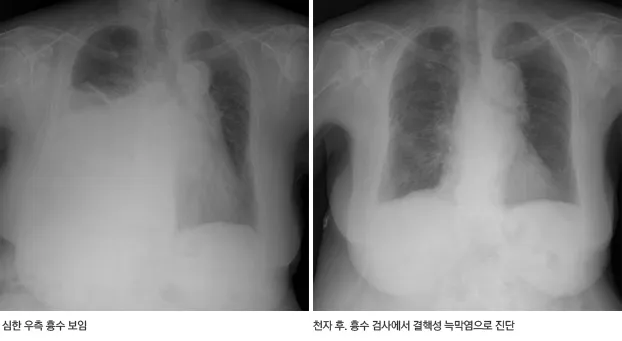

또 하나 중요한 포인트는 “한쪽만 계속 반복되느냐, 양쪽에 번갈아 생기느냐”입니다.

한쪽 폐 주변으로만 반복적으로 흉수가 생기면 결핵성 늑막염이나 암성 흉수 가능성을, 양쪽으로 넓게 생기면 심장·간·신장 기능 문제 가능성을 의료진이 더 집중해서 보게 됩니다.:contentReference[oaicite:13]{index=13}

4단계, 흉강천자(흉수 검사 및 배액)입니다.

국소마취를 하고 바늘이나 가는 관을 통해 흉막 사이에 고인 액체를 일부 또는 상당량 뽑아내면서, 단백질·당·염증수치·암세포 유무 등을 검사해 여출성인지 삼출성인지, 감염성인지 악성인지 등을 감별합니다.:contentReference[oaicite:23]{index=23}